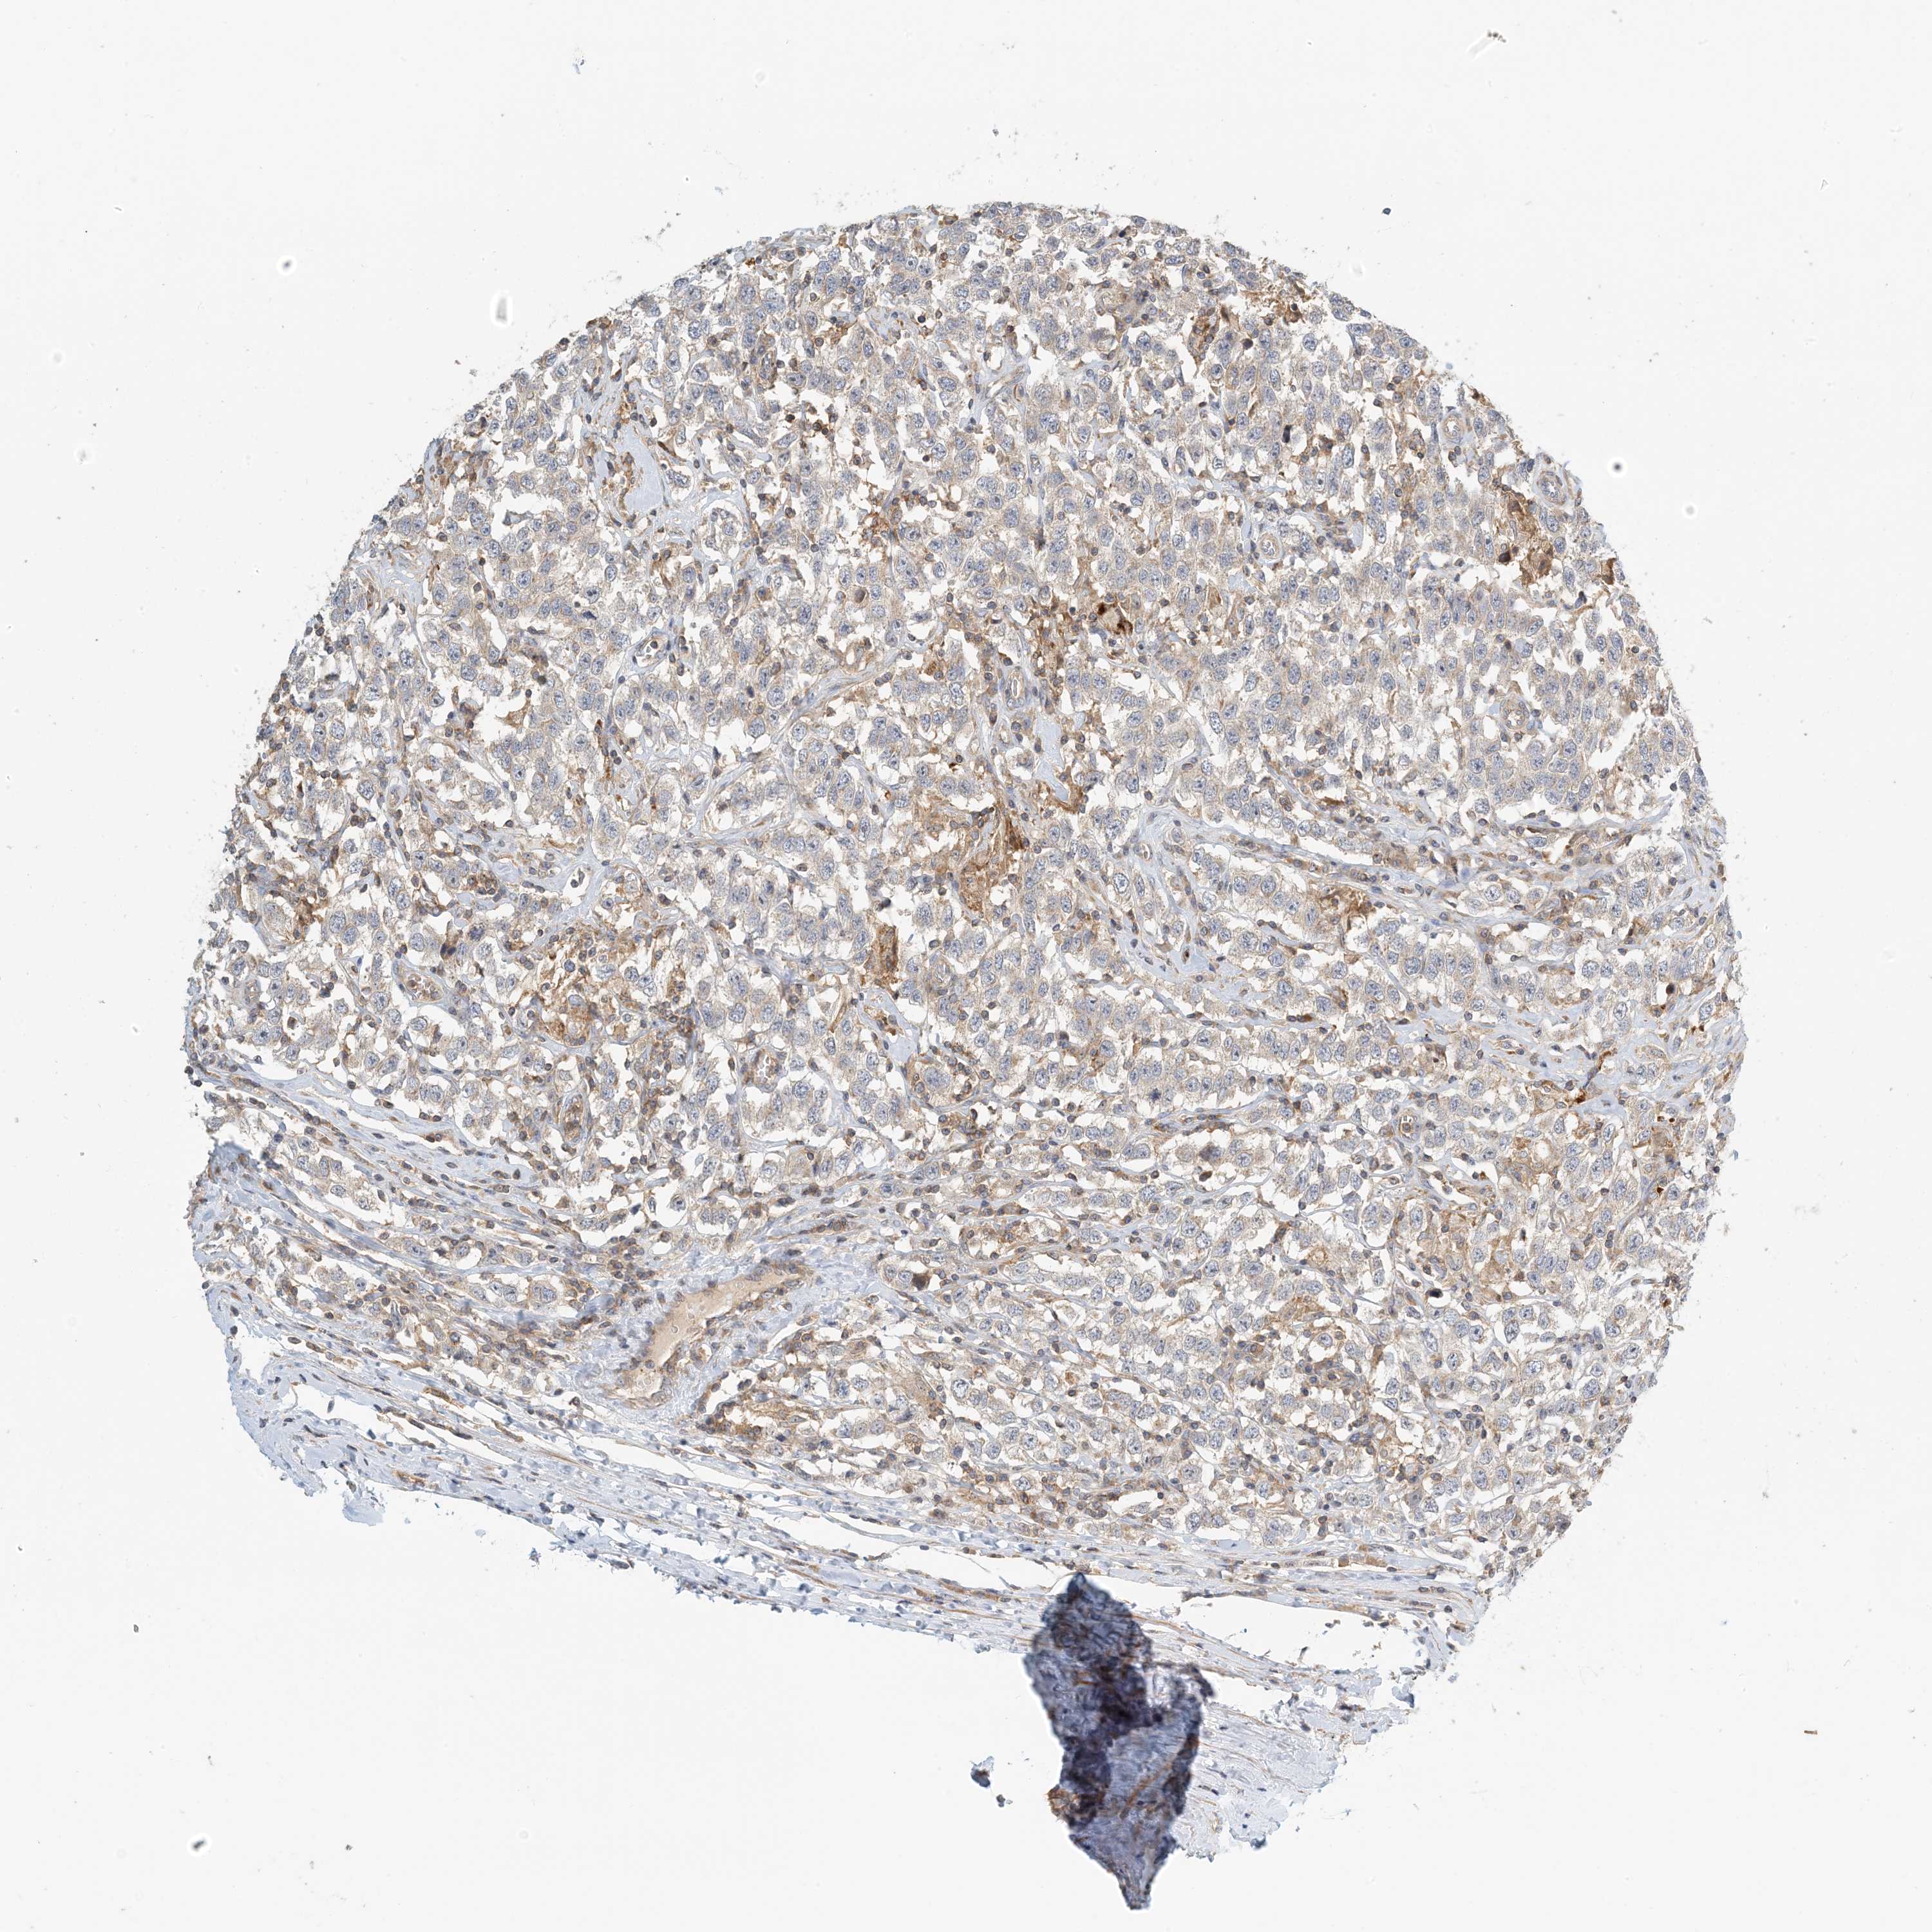

TESTIS CANCER - Protein expressioni

A mouse-over function shows sample information and annotation data. Click on an image to view it in a full screen mode. Samples can be filtered based on level of antibody staining by selecting one or several of the following categories: high, medium, low and not detected. The assay and annotation is described here.

Note that samples used for immunohistochemistry by the Human Protein Atlas do not correspond to samples in the TCGA dataset.

Antibody stainingi

Antibody staining in the annotated cell types in the current human tissue is reported as not detected, low, medium, or high, based on conventional immunohistochemistry profiling in selected tissues. This score is based on the combination of the staining intensity and fraction of stained cells.

Each image is clickable and will lead to virtual microscopy that enables deeper exploration of all samples and also displays staining intensity scores, fraction scores and subcellular localization as well as patient and tissue information for each sample.

Antibody HPA035241

Staining

High

Medium

Low

Not detected

Intensity

Strong

Moderate

Weak

Negative

Quantity

>75%

75%-25%

<25%

None

Location

Nuclear

Cytoplasmic/membranous

Cytoplasmic/membranous,nuclear

Carcinoma, Embryonal, NOS

Seminoma, NOS

Urothelial carcinoma, High grade